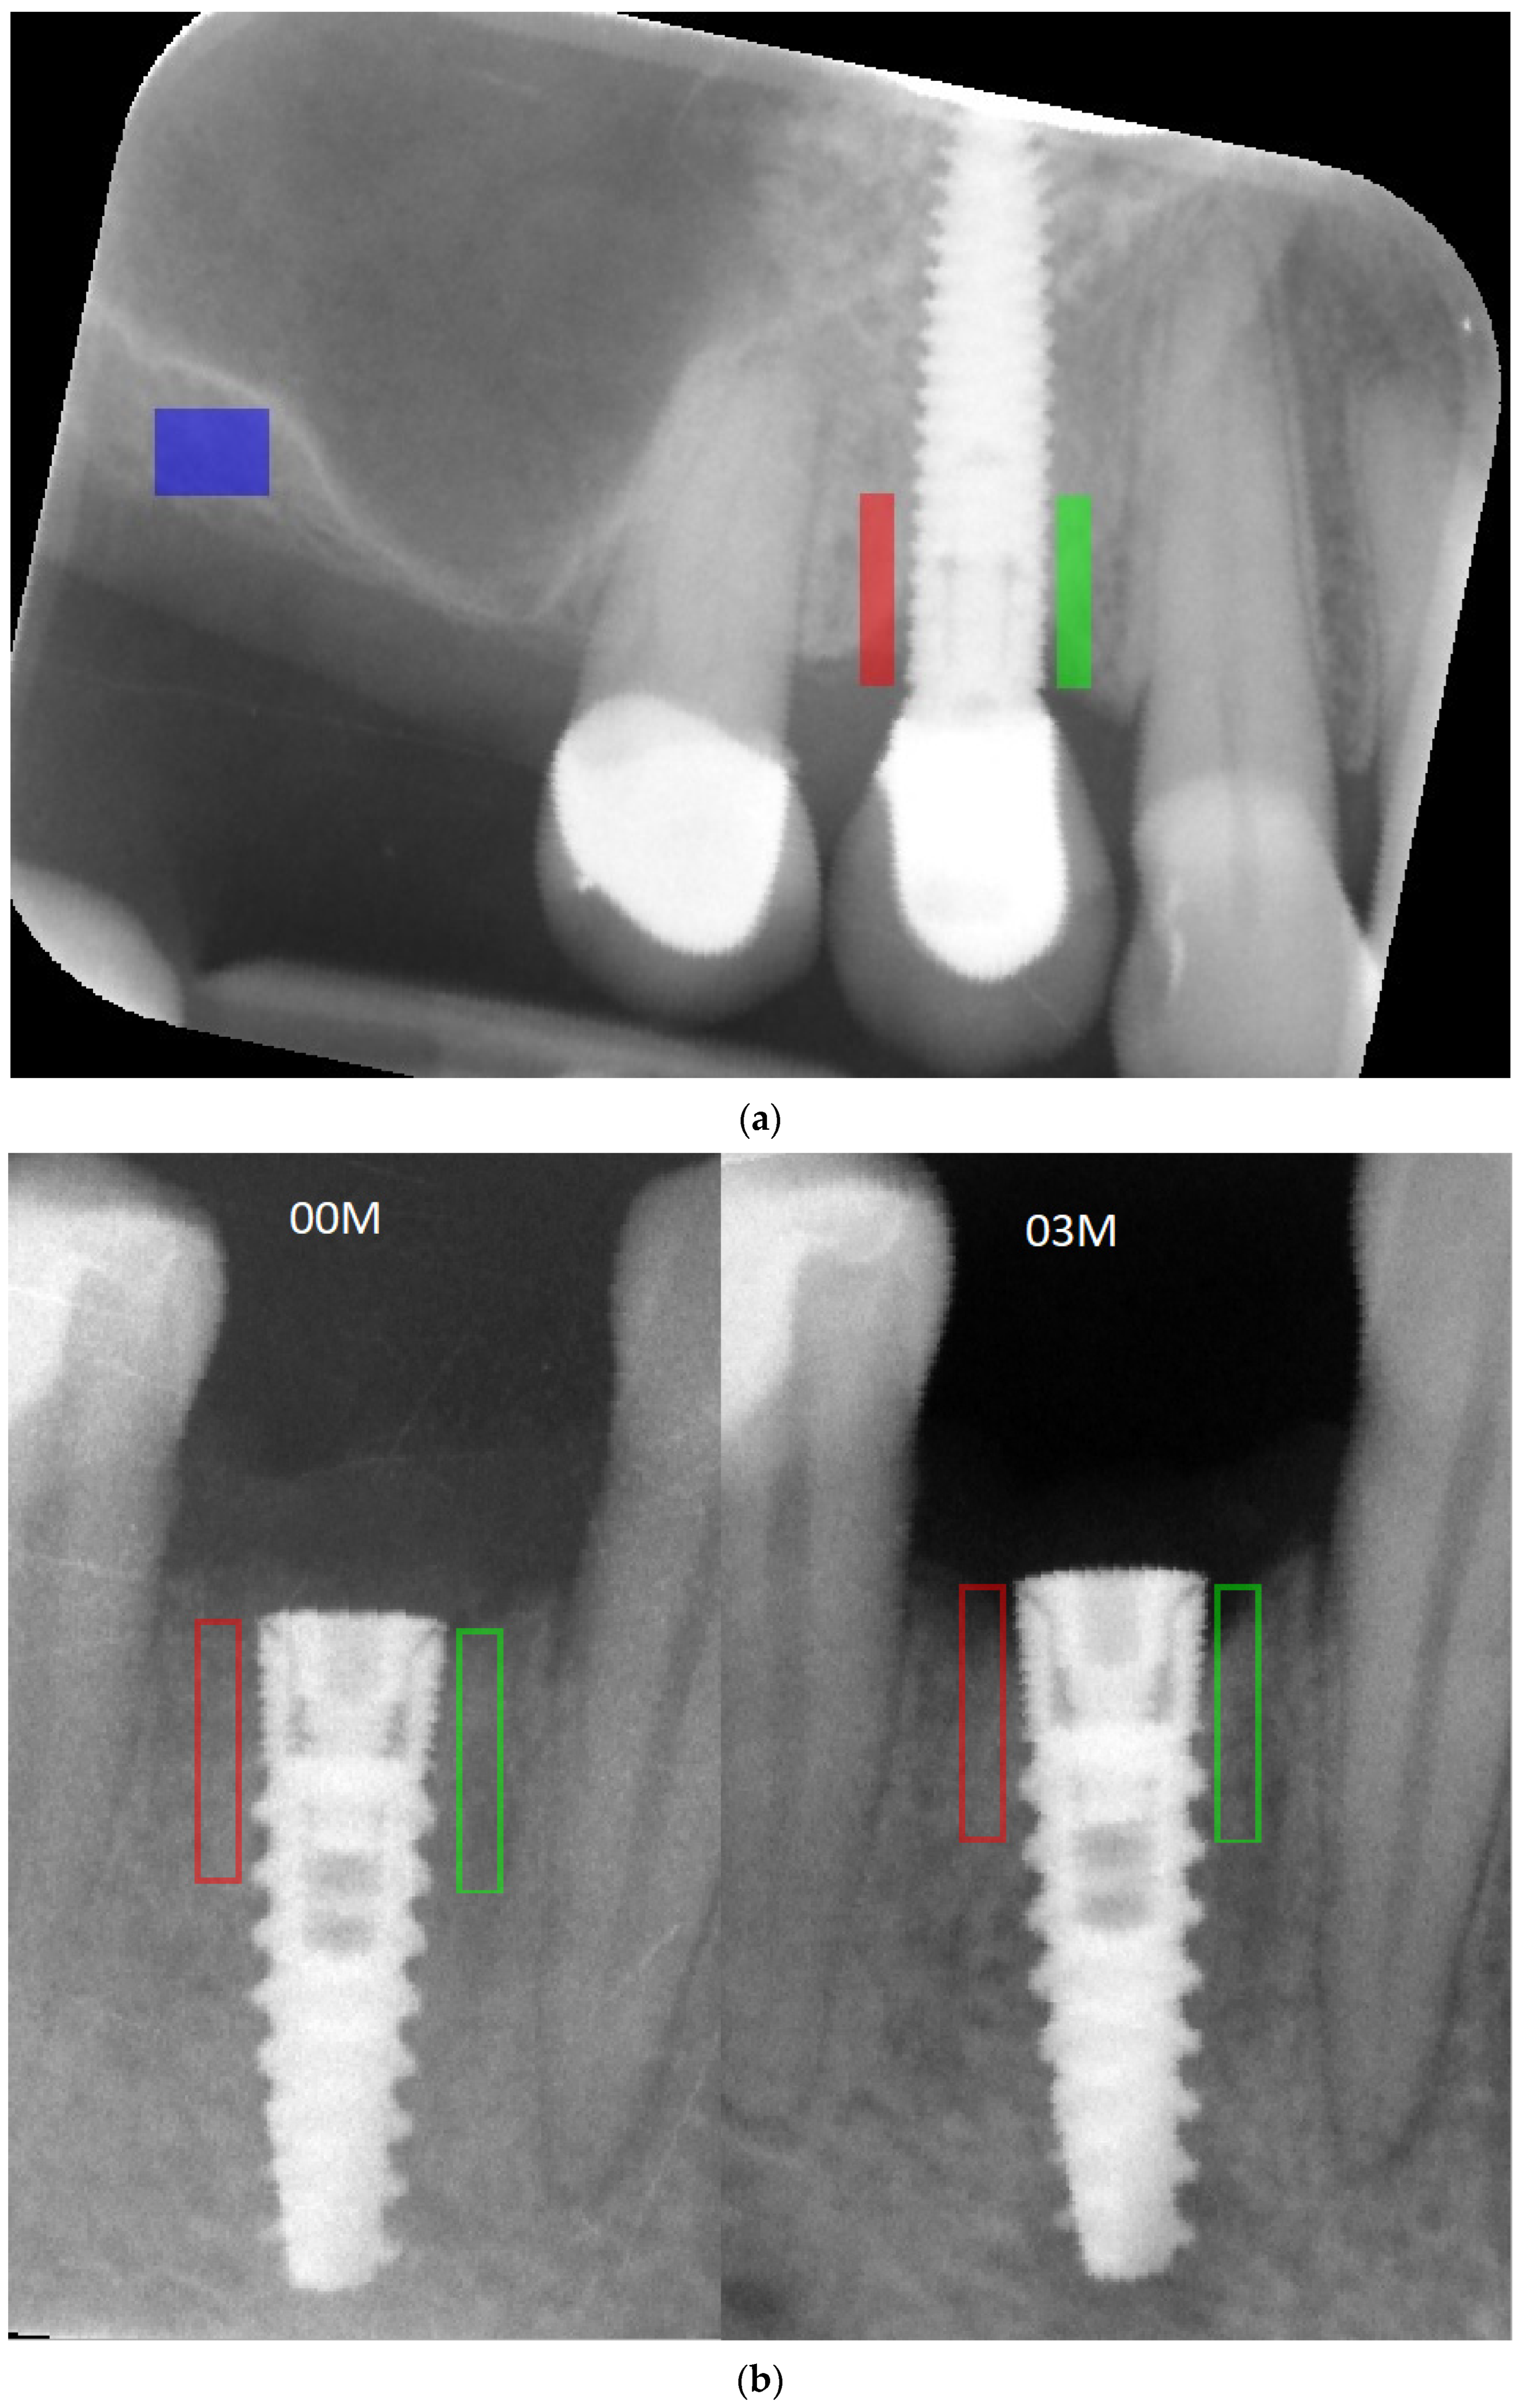

Figure 3.

(a) Marking a ROI. ROIs were marked near the implant neck area. Green area—mesial implant neck area; red area—distal implant neck area; blue area—reference bone. Abbreviations: ROI—region of interest. (b) Marking a region of interest on RTG image immediately after inserting the implant and 3 months after the first stage of the healing process. Green area—mesial implant neck area; red area—distal implant neck area. At the bottom of the marked area on the right (03M), it can be noticed that MBL occurred and is analyzed. Abbreviations: MBL—marginal bone loss; 00M—0 months of observation; 03M—3 months of observation.